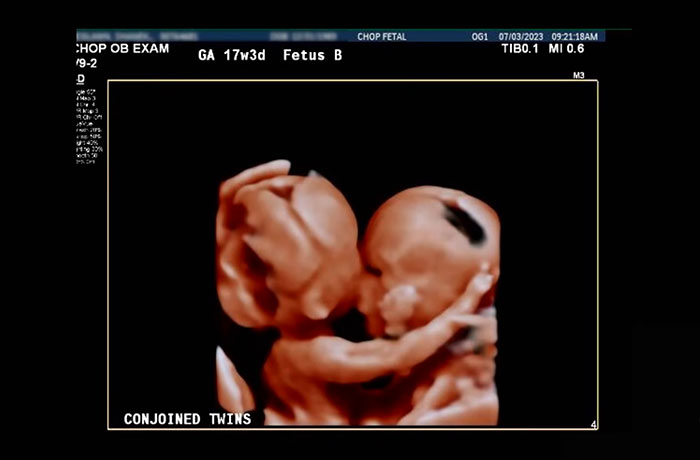

The Ruffins reportedly learned that Amari and Javar were conjoined during a routine ultrasound. Within days, they’d already met with a team and they soon learned that separation would be possible.

The twins reportedly shared the lowest part of their sternum, diaphragm, abdominal wall, and liver. The hospital explained in an official statement: “This set in motion the plan for preparing the boys’ first milestone: a safe birth.”